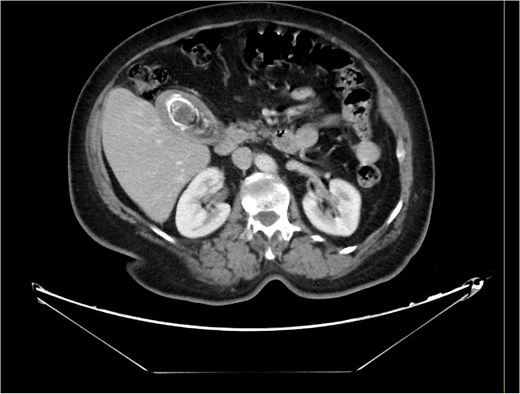

A 63-year-old obese female, known to have hypertension and diabetes, was admitted electively for laparoscopic cholecystectomy and laparoscopic incisional hernia repair with mesh. Prior to surgery, the enhanced computed tomography scan revealed a fat- containing supraumbilical hernia measuring 1.5 cm, a 54 mm gallbladder stone, and unremarkable liver pancreas, spleen, kidneys, and pelvis organs, with no evidence of intra-abdominal free air or fluid (Figs 1 and 2). The patient underwent surgery under general anesthetic using standard sterile procedures. We began with a supraumbilical incision ⁓3 cm above the umbilicus over the previous hernial site. After making a 1 cm longitudinal incision, we identified and opened the fascia, introducing a 12 mm port without immediate complications. The camera was inserted, gas was insufflated, and the abdomen was explored, revealing no immediate injury. An additional 11 mm port was inserted in the left upper quadrant for further exploration. Severe adhesions of the small bowel to the abdominal wall were noted. The first port was examined, and no bowel injury was found. LigaSure was utilized for adhesiolysis, followed by the insertion of two 5 mm ports in the right upper and lower quadrants, and a 5 mm port in the epigastric area. Laparoscopic adhesiolysis was performed, releasing the adhesions without bowel injury. The gallbladder, severely adhered to the liver bed, was identified, retracted cephalad, and Calot’s triangle was achieved. The cystic duct was identified, double clipped, and divided, followed by dissection, clipping, and division of the cystic artery. Intraoperatively, we consulted a senior consultant to confirm the anatomy. The critical view of safety was achieved, and the gallbladder was dissected from its bed. Spillage of gallbladder contents occurred, which was suctioned and controlled. The gallbladder was retrieved through the supraumbilical port using an Endobag without complications (Figs 3 and 4). Hemostasis was secured after examining the liver bed, followed by multiple irrigations and suctioning. The hernial defect was examined and found to be a small incisional hernia (⁓1 × 0.2 cm) containing only fat. After releasing the adhesions, a mesh was applied, tailored to the defect size, and secured with endo-tuckers. Hemostasis was ensured, and a JP drain was inserted under vision and secured with Prolene. All parts were removed under vision, and the skin was closed using clips. The patient tolerated the procedure well and was transferred to the Post Anesthesia Care Unit in stable condition.

Computed tomography of the abdomen and pelvis before the procedure.

Computed tomography of the abdomen and pelvis showing a 54 mm gallbladder stone.